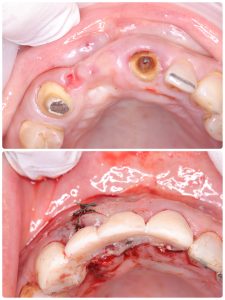

CTG

午前は、インプラントオペ

conbination tissue graft 上結節から結合組織採取

後にスーパーボンドでカバー

これがベストなやり方、痛みがない

スーパーボンドは万能

CK2ナイフにて、エンベロップ切開、カンガルーの袋作る

このような、軟組織のマネージメント移植やら仮歯、暫間インプラント、即時荷重料金も無し